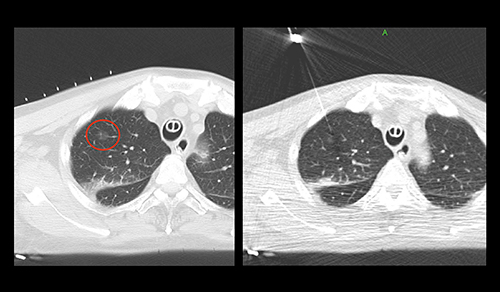

Artis zeegoの術中コーンビームCT(syngo DynaCT)は有益なデータを提供するが,密度分解能が格段に高いCTの臨床でのメリットは大きい。脳神経外科では,急性硬膜下血腫の手術の際に,開頭したままCT撮影を行い,血腫の取り残しなどを確認して進めている(図4)。呼吸器外科では,“全身麻酔下肺腫瘍マーキング”(図5,6)を行っている。通常であればCT室で局所麻酔による穿刺,胸腔鏡下手術(VATS)用のVATSマーカーの留置や色素によるマーキングを行い,その後手術室に移動して全身麻酔となる。当院では全身麻酔後にCT透視下マーキングが可能で,患者への負担も軽減できる。また,肝臓外科の直腸がん肝転移巣の切除では,化学療法が著効し,エコーなどの画像上で確認できなくなった腫瘍を切除する際に,開腹して肝臓の腫瘍があると思われる部分に直接針を穿刺し,その状態で術中CTを撮影。針の位置を目安として肝腫瘍の切除術を行っている。

図5 呼吸器外科における全身麻酔下肺腫瘍マーキング

図6 図5の全身麻酔下CT透視画像